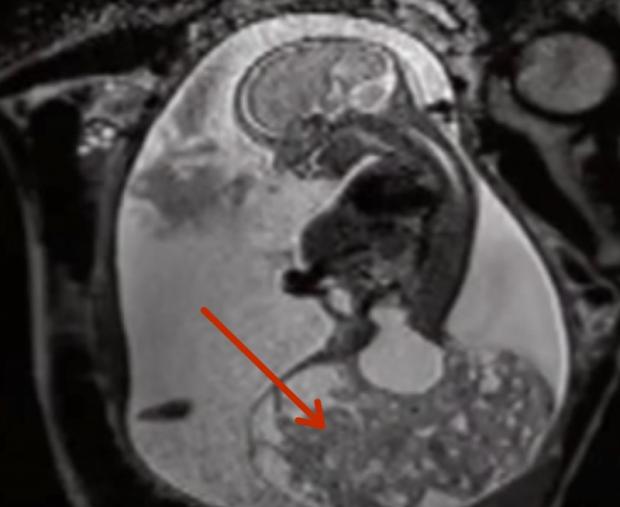

Pe parcursul multor ani americanca Keri McCartney și soțul ei Chad au trăit fericiți împreună. Ei aveau patru copii și se pregăteau de nașterea celui de-al cincilea micuț. În săptămâna 23 de sarcină Keri s-a dus la spital ca să facă un consult ecografic. Însă după ce au examinat-o, medicii i-au dat o știre îngrozitoare: examenul ecografic a arătat că copilul are o tumoră gigantă, care aproape depășea prin dimensiunile sale corpul micuțului! Medicii nu mai văzuseră așa ceva, scrie punct.tv.

Cu toate că era benignă, tumora era periculoasă datorită mărimii sale uriașe, deoarece priva copilul de toate forțele vitale, tulburând în mod esențial fluxul sanguin.

Pentru a salva viața micuțului, medicii au hotărât să îndepărteze tumora chirurgical, fără să întrerupă sarcina. Și cu toate că probabilitatea unui rezultat pozitiv era de doar 10%, Keri a decis să riște.

Operația a durat 4 ore. Pentru relaxarea completă a uterului a fost necesară o anestezie de 7 ori mai profundă decât în operațiile obișnuite. Ca să fie incizat fără lezarea placentei, uterul a fost scos în totalitate din cavitatea abdominală a lui Keri. Din incizie au fost extrase fătul și tumora, în uter rămânând doar capul. Apoi tumora a fost îndepărtată, iar viitorul copil, care a stat în afara uterului aproximativ 20 de minute, a fost introdus înapoi în corpul matern.